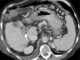

Non-cirrhotic portal hypertension

Portal hypertension is hypertension (high blood pressure) in the hepatic portal system – made up of the portal vein and its branches, that drain from most of the intestine to the liver. Portal hypertension is defined as a hepatic venous pressure gradient. [Source: Wikipedia ]